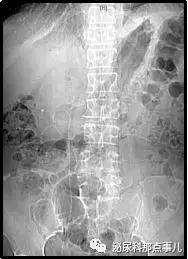

术后CT